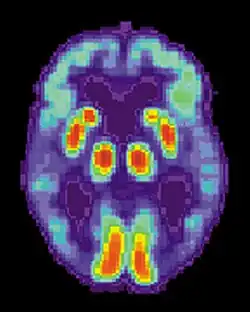

Scan par TEP d'un cerveau en bonne santé.

Scan par TEP atteint de la MA.